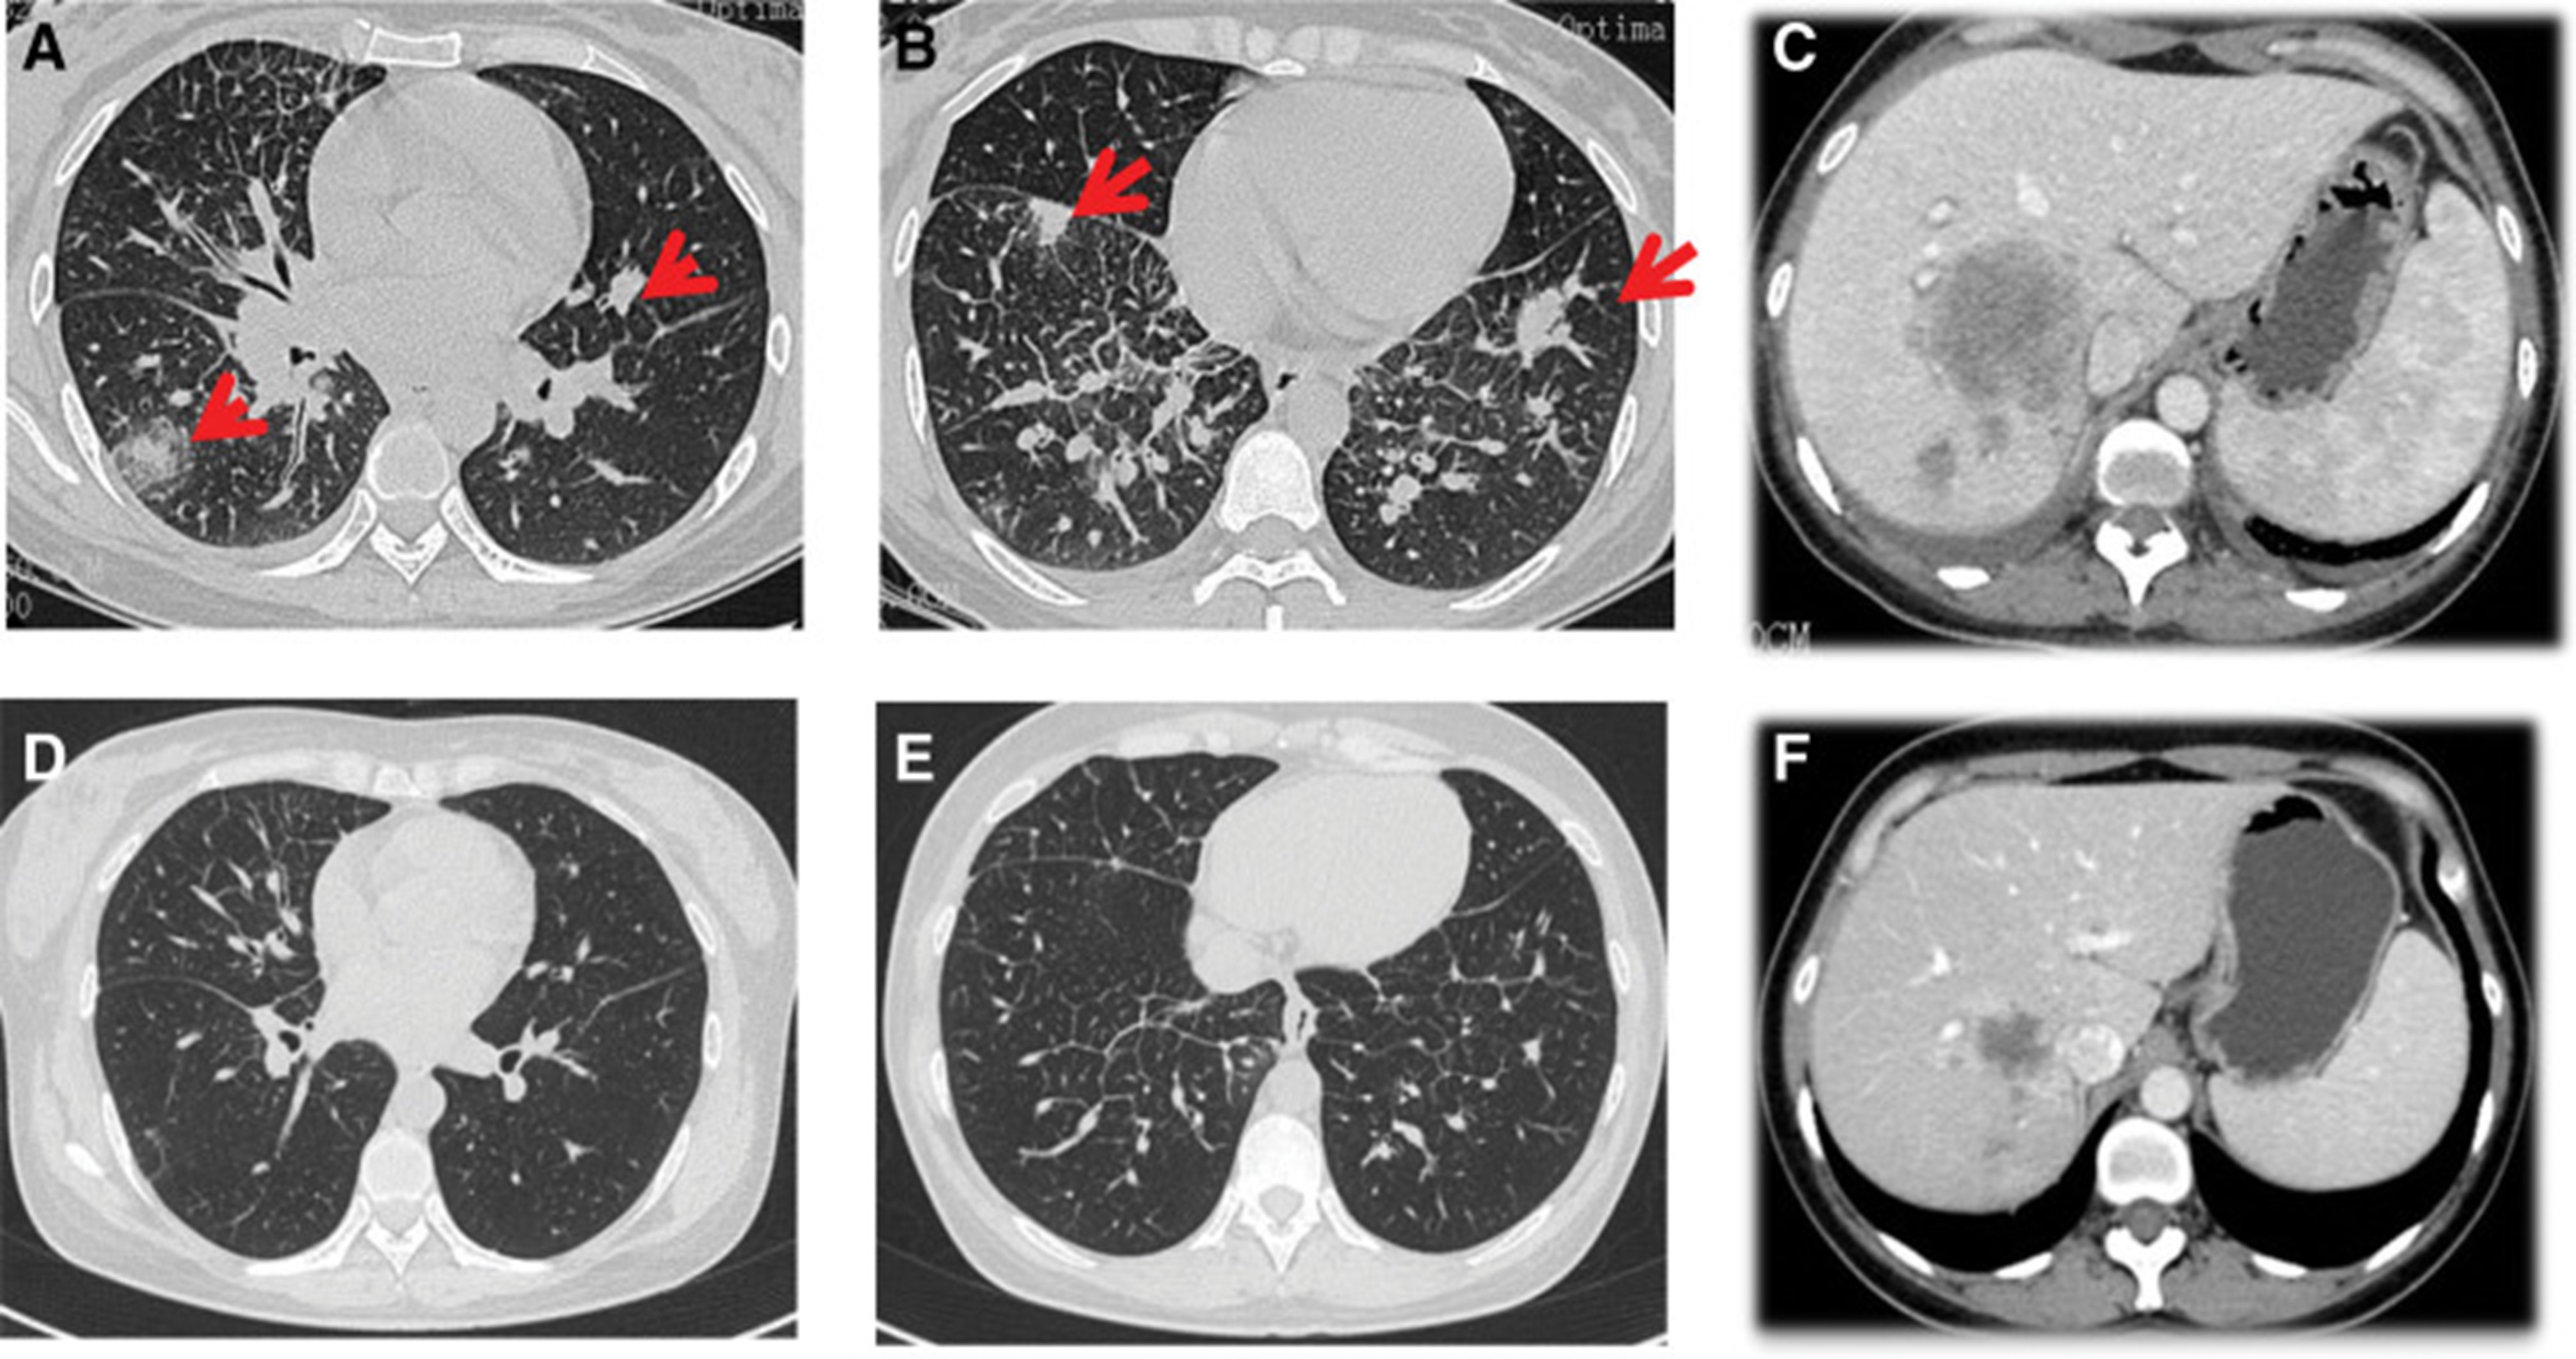

2020年5月1日,患者开始口服艾乐替尼靶向药物进行治疗,2020年6月25日复查,确定治疗效果为PR(部分有效)(根据RECIST1.1)显示肺病灶和肝转移灶明显减少(图1)。(图 3D-F)。2020 年 8 月 27 日复查确定治疗效果为疾病进展(PD, progressive disease),根据 RECIST1.1显示肝脏病变变大(图 1)(图 4A-D)。进行了第二次肝活检,随后的病理学显示“(肝)低分化癌,结合免疫组织化学分析考虑肺腺癌转移”。组织活检进行了第二轮基因检测,结果显示“BRAFV600E 14.79%,EML 4-ALK fusion 14.47%”(图 1)(图 5)。2020年9月20日,对患者我以为用恩沙替尼联合达拉非尼靶向治疗。治疗开始后,患者出现明显发热、寒战、乏力和厌食。期间患者左侧出现大量胸腔积液,胸腔积液中脱落细胞为“非典型细胞,考虑为腺癌”。随后,该患者接受了 1 次胸腔内铂输注。

和 2020 年 8 月.jpg)

图 5:2020 年 6 月(A 和 B)和 2020 年 8 月(C 和 D)的 CT 扫描。CT = 计算机断层扫描。

1个月后复查显示肺部和肝内病变进展(图1)。(图 6A-C)(根据RECIST1.1),她的抗肿瘤治疗改为“培姆曲塞加卡铂和贝伐单抗”的治疗一个周期。2020年12月至2021年1月,再次改变患者的治疗方案,这次改为“劳拉替尼联合达拉非尼”靶向治疗。使用 PD 联合胸部和腹部 CT 评估疗效(图 1)。(图 6D-F)(根据 RECIST1.1)。患者无法耐受化疗、靶向治疗、IO 治疗或任何其他积极的抗肿瘤治疗。这是因为患者的一般情况较差,包括发烧、腹痛和胆红素水平升高等症状。随后,给予患者静脉营养、镇痛等对症支持治疗。患者于 2021 年 2 月 4 日去世,总生存期(OS)为 10 个月。

和 2022 年 1 月 (D-F) 的 CT 扫描.jpg)

图 6:2020 年 11 月 (A-C) 和 2022 年 1 月 (D-F) 的 CT 扫描。CT = 计算机断层扫描。